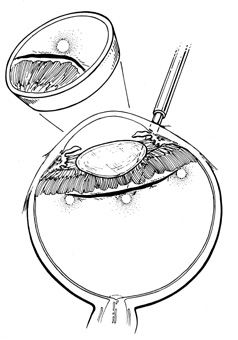

Isolation of the four rectus muscles usually allows adequate access to all areas of the sclera necessary to perform scleral buckling. Rarely, however, a muscle must be removed to adequately expose an area. This usually occurs with breaks beneath muscles or in eyes with tight or small orbits. After the muscle has been isolated, it is elevated with a muscle hook, and a double-armed absorbable synthetic 5-0 or 6-0 suture is passed through the body of the muscle parallel to the insertion and just posterior to the hook. A central knot may be placed. The suture is then passed in a single or double loop through the end of the muscle to occlude the anterior ciliary arteries. With both the suture and hook used for traction, the muscle is elevated from the sclera and cut, leaving a small portion of insertion intact on the sclera. The arms of the suture are secured, and the muscle is allowed to retract posteriorly. A 4-0 silk traction suture is placed through the insertion with at least two passes. After completion of scleral buckling, the muscle is repositioned to the insertion with the double-armed suture (Fig. 4).

Fig. 4. A to C. Technique for removal and replacement of rectus muscle.